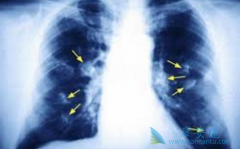

肺癌,是目前全人类的杀手。在我国肺癌是发病率和死亡率双高的恶性肿瘤。从19世纪起,人类陆续开始尝试用手术、放射、化疗等方式来治疗肺癌,但是效果并不理想。大量临床数据表明,肺癌早期的5年生存率高达70%~80%以上,而晚期肺癌的5年生存率为5%以下。 ...

肺癌患者往往发现的时候已经是中晚期了,早期肺癌症状类似感冒咳嗽,很容易被患者忽视,不治疗身体也没出现大的问题,就没在意,当几年后突然检查时,医生告知肺癌晚期。那么, 晚期肺癌能治吗 ?当然是可以的,肺癌晚期可以选择外科的治疗,比如放射性 ...

现在大家都谈癌色变,一旦得了癌症就觉得离死不远了。其实,随着检查手段和医疗技术的发展,很多癌症现在都是可以治愈的,就算是一些不能治愈的癌症,也可以通过一系列的治疗实现带瘤生存。以肺癌为例,如果患者能够在早期发现病情,一般手术加上一些辅 ...